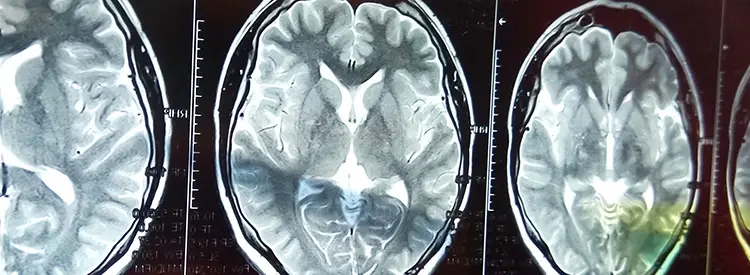

Un accidente cerebrovascular ocurre cuando se corta el flujo sanguíneo a una parte del cerebro. Cuando eso ocurre, el tejido cerebral que pierde su suministro de sangre se lesiona o muere. Esto da como resultado una pérdida de función en el cuerpo en función de lo que controla el área dañada del cerebro. Por ejemplo, si el área que controla el movimiento del brazo izquierdo está dañada, ese brazo se debilitará o paralizará. Si el área que controla la sensibilidad en el brazo izquierdo también está afectada, el brazo estará entumecido o puede tener sensaciones de ardor o dolor también. Dado que el cerebro controla todos nuestros movimientos y sensaciones, incluida la vista y el habla, casi cualquier cosa puede verse afectada por un accidente cerebrovascular.

En general, existen dos tipos de accidente cerebrovascular, isquémico y hemorrágico. Los accidentes cerebrovasculares isquémicos son los más comunes. Los accidentes cerebrovasculares isquémicos ocurren cuando el vaso sanguíneo que va a una parte del cerebro se bloquea, generalmente por un coágulo de sangre o una acumulación de colesterol similar a un ataque cardíaco.

Los accidentes cerebrovasculares hemorrágicos son la forma menos común de accidente cerebrovascular. Se producen cuando un vaso sanguíneo pierde líquido y hay sangrado dentro y alrededor del cerebro. Saber qué tipo de accidente cerebrovascular está presente es esencial para el tratamiento temprano del accidente cerebrovascular.

El tratamiento del accidente cerebrovascular ha mejorado sólo lentamente. Si se trata en los primeros minutos, el daño causado por un accidente cerebrovascular isquémico se puede revertir o limitar utilizando medicamentos especiales (alteplasa o activador tisular del plasminógeno) en una sala de emergencias o en un hospital. Este medicamento puede romper el coágulo que bloquea el vaso sanguíneo. Si se utiliza en los primeros minutos u horas, puede evitar o limitar cualquier daño al cerebro. Es esencial que se realice una tomografía computarizada para determinar el tipo de accidente cerebrovascular y confirmar que no es hemorrágico antes de utilizar alteplasa. Dado que la alteplasa rompe un coágulo, puede causar un empeoramiento grave o la muerte si se utiliza con un accidente cerebrovascular hemorrágico. Los accidentes cerebrovasculares hemorrágicos a veces se tratan para evitar una mayor hemorragia.